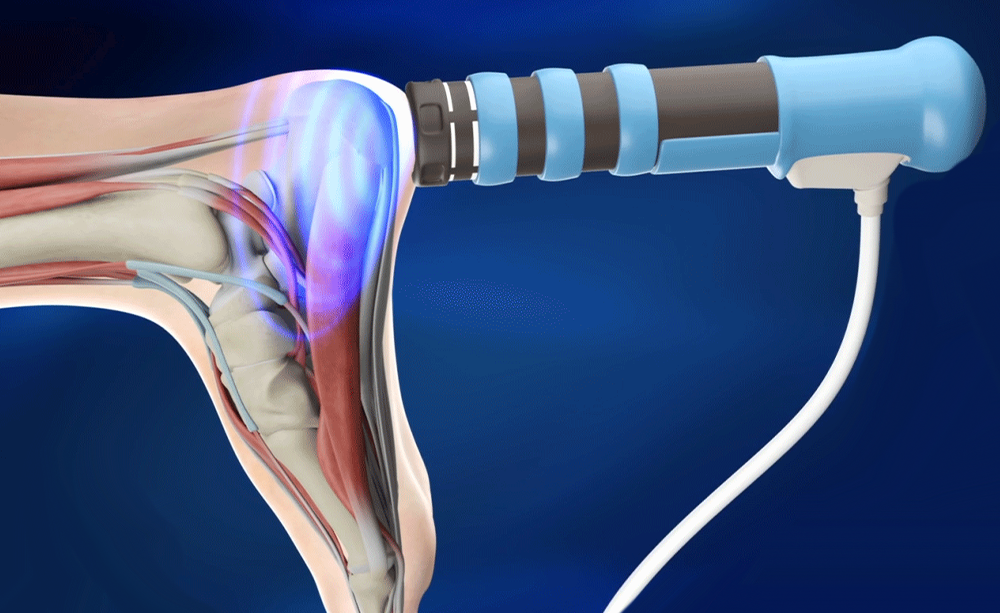

Cupping Therapy